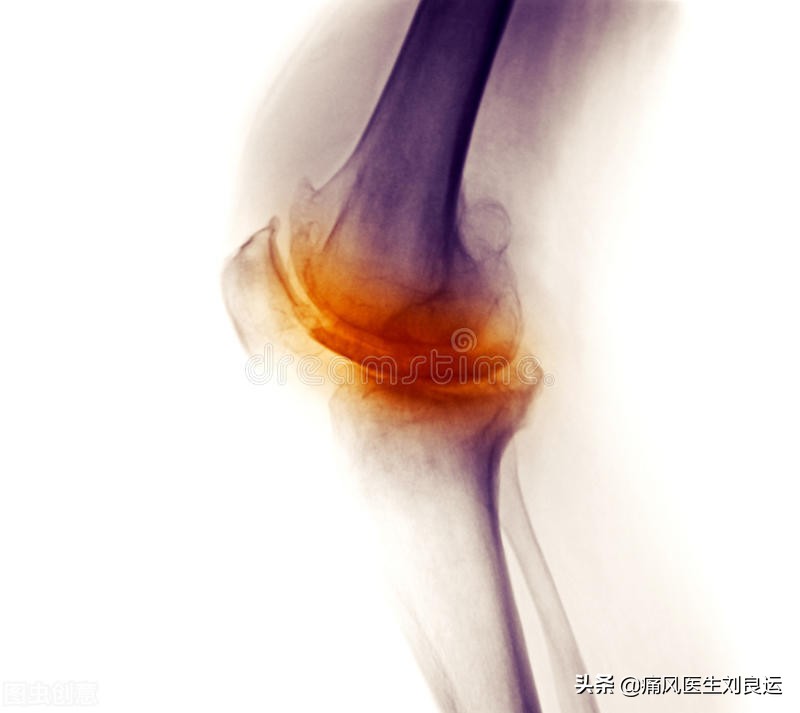

膝关节严重退行性关节炎病变